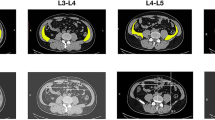

We identified and correctly position the L4–L5 intervertebral space in the coronal plane, and outlined the boundaries of “the working triangle” as suggested by Hardenbrook [16]. The hypotenuse of the triangle corresponds to the exiting nerve root, the base to the upper edge of the pedicle, and the height to the traversing nerve root. We then sketched Kambin’s triangle on the CT scan, and drew a circle within the triangle, labelling its centre as point ‘O,’ and measured the diameter, ‘d’ (in millimetres) of the inscribed circle. This diameter represents the maximum diameter of the visible trephine in the surgical field (Fig. 1).

Kambin’s triangles on both sides of the L4–L5 intervertebral space. Images show the coronal plane, including the inscribed circles. AB, exiting nerve root; AC, traversing nerve root; BC, horizontal line at the upper edge of the pedicle; O, centre of the inscribed circle in Kambin’s triangle.Diameter of the inscribed circle in a right triangle = Base + Height − Hypotenuse (mm)

On the sagittal plane, we adjusted the axis to ensure the horizontal baseline was parallel to the upper endplate of the L5 vertebra. We then elevated the horizontal baseline to align with the L4–L5 intervertebral space, thereby centring the plane on the intervertebral disc in the transverse section. A rectangle was then constructed by drawing tangents to the anterior, posterior, left, and right edges of the disc. The diagonals of the rectangle were connected to locate the centre of the intervertebral disc, labelled as point ‘D.’ From ‘D’, we traced backward to find the centre of the spinous process, defined as point ‘E,’ establishing DE as the central line. In this study, angle ‘β’ was measured between line OD, connecting centre ‘O’ with the centre of the intervertebral disc ‘D,’ and line DE, representing the trephine’s optimal abduction angle during surgery. Although centre ‘O’ is above the transverse section containing ‘D,’ the plane defined by lines DE and OD remains constant, ensuring accuracy of the measurement of angle ‘β’ on the transverse section (Fig. 2).

To enhance safety assessment, we compared the diameter ‘d’ to the commonly used 8 mm clinical diameter of a visible trephine. We then aimed to measure the shortest distance from the outer edge of the trephine, set at the ‘β’ abduction angle, to the lateral boundary of the exiting nerve root within Kambin’s triangle, denoted as ‘L1’; and the greatest distance to the lateral boundary of the traversing nerve root, denoted as ‘L2’. These measurements represent the safe distances of the visible trephine from the exiting and traversing nerve roots when establishing a working channel. We posited that results of ‘L1’ and ‘L2’ ≥0 mm indicate a sufficient safety margin of an 8-mm diameter visible trephine relative to both the exiting and traversing nerve roots; larger values suggest increased safety due to greater distances from these nerve roots. A result of ≤ 0 mm suggests that the outer edge of the visible trephine has reached or breached the exiting and traversing nerve roots, potentially causing damage during surgery (Fig. 4).

Mimics 3D simulation with an 8-mm diameter visible trephine. The trephine is placed on both sides of the intervertebral space. DE, midline, extending from the centre of the intervertebral disc on the transverse section to the midpoint of the spinous process; L1, shortest distance from the outer edge of the trephine to the side boundary of the exiting nerve root within Kambin’s triangle; L2, shortest distance from the outer edge of the trephine to the side boundary of the traversing nerve root within Kambin’s triangle